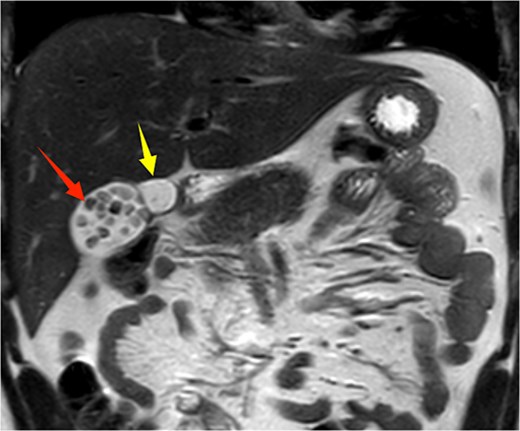

A 21-year-old male patient was admitted to our hospital with a 2-year history of intermittent right upper quadrant colicky pain. The symptoms initially occurred 2 years ago after consuming fried food, accompanied by nausea and vomiting, and were relieved after antispasmodic and analgesic treatment. Over the past 2 years, the symptoms recurred frequently, prompting the patient to seek further evaluation at our institution. The patient had no significant past medical history, including hypertension, diabetes, coronary heart disease, or other chronic conditions. He denied smoking, alcohol consumption, and any known drug allergies. Physical examination on admission revealed stable vital signs, with no jaundice observed in the skin or sclera. The abdomen was flat, with mild tenderness in the right upper quadrant and no rebound tenderness. The liver and spleen were not palpable. Murphy's sign was negative, abdominal percussion yielded tympanic sounds, and bowel sounds were normal. Laboratory tests, including complete blood count, liver function (bilirubin, ALT, AST, etc.), coagulation profile, amylase, lipase, and infection markers, were all within normal limits. Ultrasonography indicated multiple gallstones, a thickened and indistinct gallbladder wall, and suspicion of a folded gallbladder or possible double gallbladder malformation. To further delineate the biliary anatomy and ensure surgical safety, an abdominal MRI was performed. Magnetic resonance imaging (MRI) confirmed a double gallbladder malformation, with multiple stones in the lateral gallbladder (Figs 1 and 2). The clinical diagnosis was established as cholelithiasis with double gallbladder malformation.

Upper abdominal MRI coronal view demonstrates a double gallbladder variation. The two arrows indicate the respective gallbladders, the lateral one of which contains multiple gallstones.